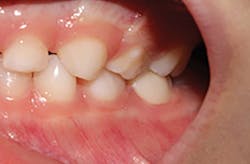

The following case study is presented to illustrate the ease of tooth preparation and crown cementation: A 5-year-old patient presented with caries of her primary dentition. The mandibular left primary molar required full coverage due to a failed composite restoration and extensive decay (figure 1). Both the child and her mother had a desire for a tooth-colored restoration. A primary prefabricated zirconia crown (NuSmile ZR) was chosen as the restorative material of choice.

Figure 1: Mandibular left primary molar